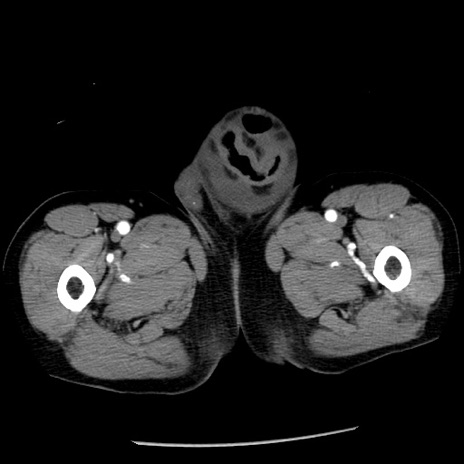

冠状断像